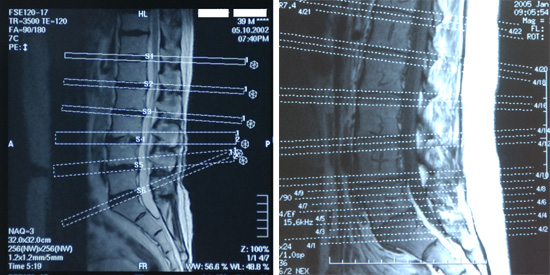

最近、患者さんから提供されたMRI画像(写真・右)を見て、ため息と困惑が生じました。通常のMRI画像(写真・左)と比較し説明します。MRIは身体のあらゆる角度の断面画像を容易に得ることができます。

この画像は腰椎椎間板の状態(ヘルニアによる脊髄や神経根の圧迫など)を診断する目的で、人体の水平方向断面画像を撮影した時に添付されるマップ画像です。このマップ画像により、断面画像の部位や角度を知ります。腰椎椎間板の情報を得るためには、目的の腰椎椎間板に対し水平方向の画像が必要なはずですが・・・左右のマップ画像を比較すれば、ため息理由が想像できると考えます。

患者から報告された、医師の患者対応にさらに困惑しました。画像を見ながら「うん・うん」とつぶやいた後に「シップを出しておく、もっと痛くなったら来なさい」と告げられただけで、MRI画像についての説明は全くなかったとのことです。画像に残る腰椎部の“手書き数字”の必要性が全く理解できません。